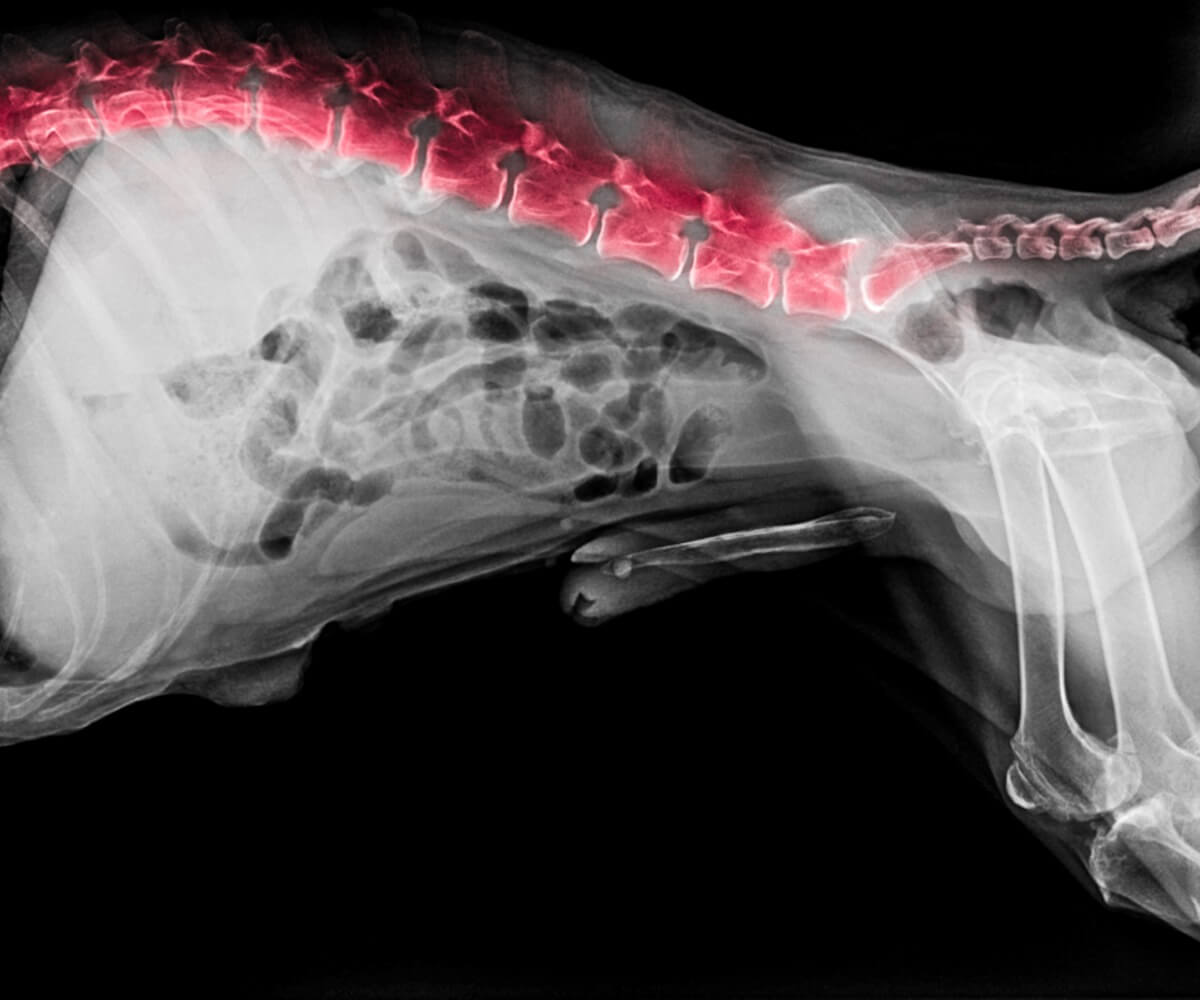

Metodi diagnostici

Come avrete notato, i problemi alla schiena nei cani sono molto simili tra loro. Pertanto, l’uso di strumenti diagnostici sarà di grande aiuto per definire il processo che attraversa l’animale domestico. Le principali e più efficaci metodiche diagnostiche attualmente utilizzate in clinica sono le seguenti:

- Piastre radiografiche (con o senza mezzo di contrasto).

- Tomografia computerizzata.

- Risonanza magnetica.

- Campionamento (liquido cerebrospinale).